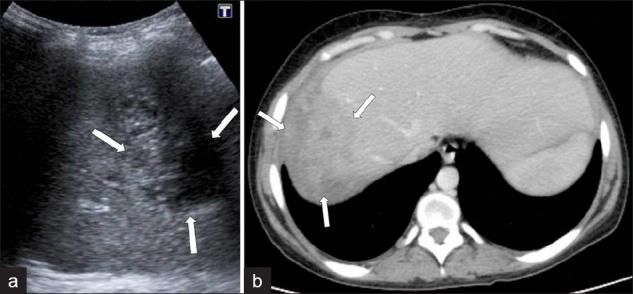

Fascioliasis refers to a zoonosis caused by Fasciola hepatica, a trematode infecting herbivores, but also occurs in humans who ingest the metacercaria found in fresh water plants. Infection in humans is common in developing countries and is also not uncommon in Europe. Diagnosis of this infection is difficult, as the history and symptoms are nonspecific and stool analysis for eggs is negative until the disease is in an advanced state by when the parasite has reached the biliary system. The clinical course consists of two phases; first a hepatic parenchymal phase in which immature larvae invade the liver parenchyma, followed by a ductal phase characterized by the excretion of larvae into the bile ducts. Parenchymal Phase: Ultrasonography (US) findings are nonspecific in this early phase. Computerized tomography (CT) may demonstrate subcapsular low attenuation regions in the liver. Magnetic Resonance imaging (MRI) can also be utilized to establish liver parenchymal involvement, and is better than CT in characterizing hemorrhagic lesions, as well as identifying more lesions relative to CT. Ductal Phase: US examination is most useful at this stage, with its ability to demonstrate the live movement of the worms within the dilated ducts. A CT demonstrates dilated central biliary ducts with periportal tracking, whereas, mild ductal dilatation is poorly appreciated under MRI. Therefore, familiarity with the multimodality imaging features of fascioliasis, in combination with an available confirmatory enzyme-linked immunoassay, would be most helpful for early diagnosis.

肝片吸虫病是一种由肝片吸虫引起的人畜共患病,这种吸虫感染食草动物,但人类摄入淡水植物中的囊蚴后也会感染。在发展中国家,人类感染这种疾病很常见,在欧洲也并不罕见。这种感染的诊断很困难,因为病史和症状不具有特异性,而且在疾病发展到晚期寄生虫进入胆道系统之前,粪便虫卵分析一直呈阴性。临床病程包括两个阶段:首先是肝实质期,未成熟幼虫侵入肝实质,随后是导管期,其特征是幼虫排入胆管。实质期:在此早期阶段,超声检查(US)结果不具有特异性。计算机断层扫描(CT)可能显示肝脏包膜下低密度区域。磁共振成像(MRI)也可用于确定肝实质受累情况,在表征出血性病变以及相对于CT识别更多病变方面比CT更好。导管期:US检查在这个阶段最有用,它能够显示扩张胆管内虫体的活动。CT显示中央胆管扩张并伴有门静脉周围条索状影,而在MRI下轻度胆管扩张不易被察觉。因此,熟悉肝片吸虫病的多模态影像学特征,并结合可用的确诊酶联免疫测定,对早期诊断最有帮助。